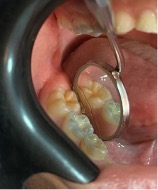

En 2015, cuando el paciente tenía 3 años y 8 meses, la madre fue en busca de explicaciones para dichas alteraciones. En la anamnesis fue relatado que los primeros dientes primarios erupcionaron alrededor de los 12 meses de edad y que la madre notó alteración del color desde el inicio, pero como la pediatra la había alertado sobre la alteración de color, no buscó rápida atención. Durante el examen clínico se observó coloración verde en todos los dientes prmarios presentes; la pigmentación se localizaba en los incisivos centrales y laterales superiores e inferiores en toda extensión de la corona hasta el tercio cervical. En los caninos inferiores la coloración verde se extendió desde el borde incisal al tercio medio de la corona. Los primeros y segundos molares inferiores y superiores estaban afectados en casi toda la extensión de la corona por un tono verde oscuro, y apenas el tercio cervical no presentaba coloración (Figuras 1 y 2). Los dientes primarios presentaron una morfología normal (esmaltes con superficies lisas y regulares), buenas condiciones de higiene bucal (bajo índice de placa dental) y ausencia de manchas blancas, lesiones de caries y de hipoplasias y movilidades. Los tejidos blandos estaban íntegros y presentaban coloración normal. En las radiografías no se observó ninguna alteración (Figura 3).

Figura 2: Imagen oclusal de los dientes. (A) Oclusal inferior y (B) Oclusal superior. Se observa pigmentación verde. Paciente con edad de 3 años y 8 meses.